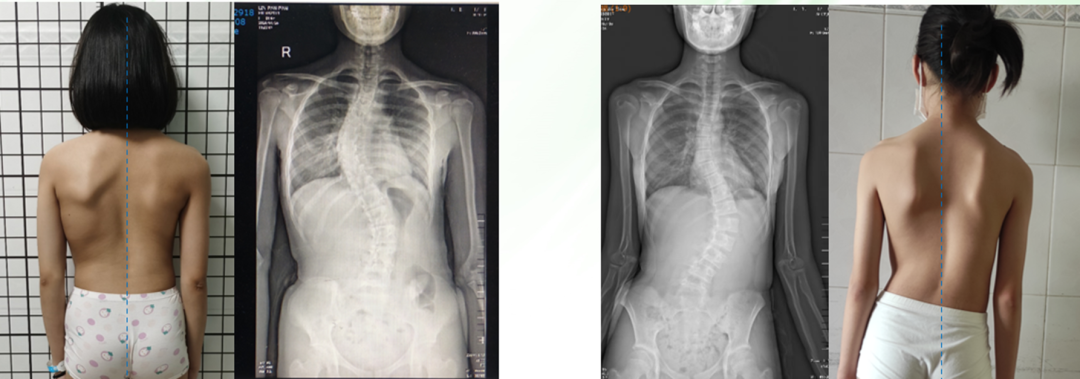

脊柱侧弯儿童示例:重点观察孩子的肩膀/肩胛骨/腰窝/骨盆

脊柱侧弯儿童